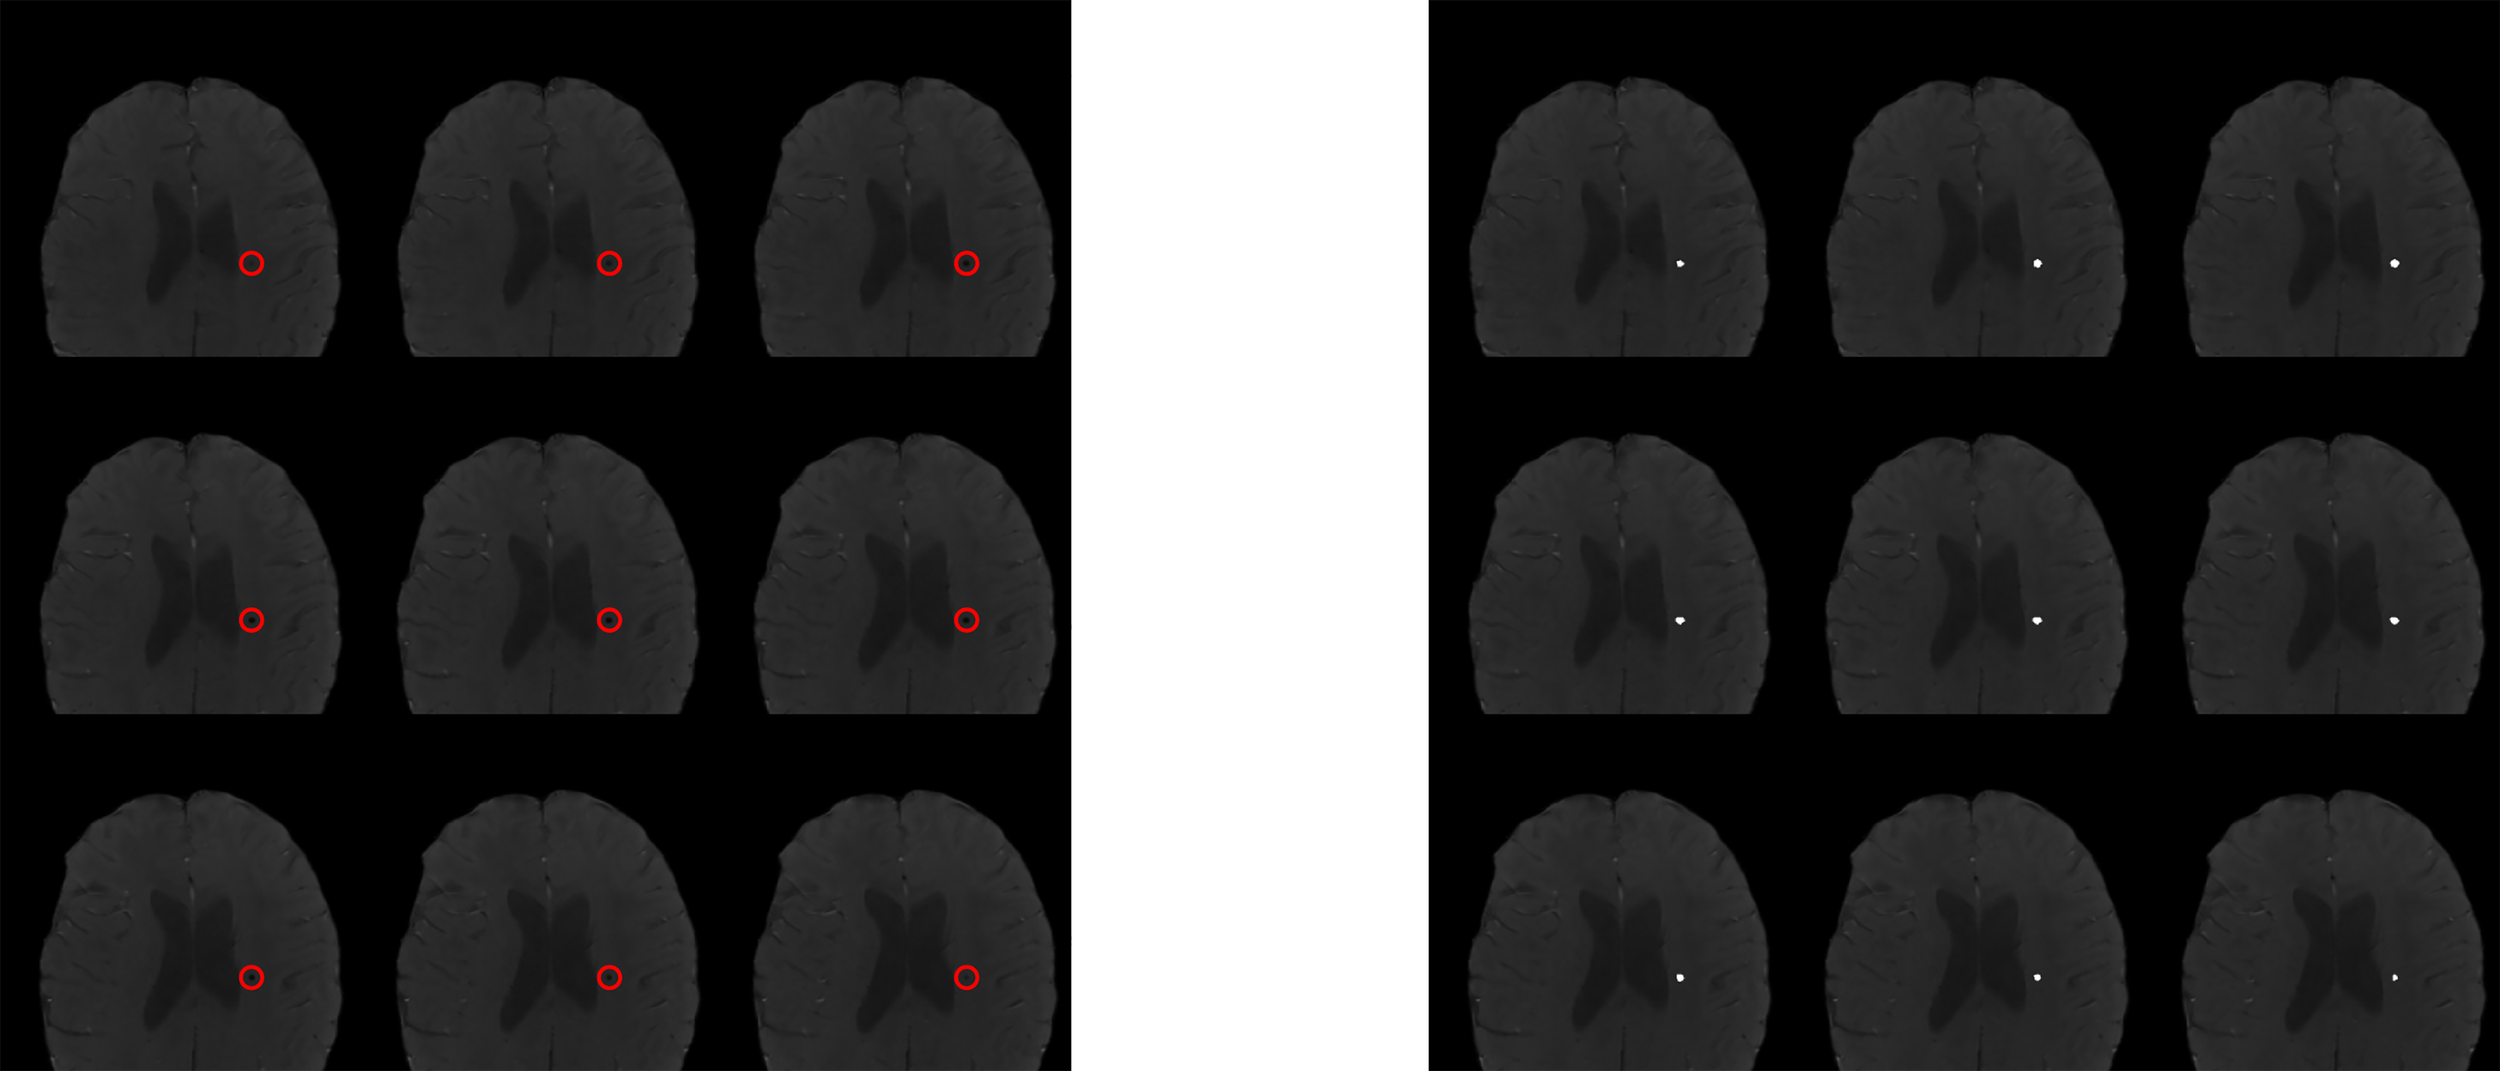

Figure 2

Visual representation of CMB analysis. Imaging inclusive of semi-automated lesion segmentation iron-sensitive sequence analysis. Left panel shows sequence without segmentation label with manually insertion of red circle outlining area of known cerebral microbleed. Right panel displays with semi-automated insertion of white circle overlying area of cerebral microbleed identified on segmentation.

Iron-sensitive imaging including T2*-weighted gradient echo sequences or susceptibility-weighted imaging (SWI; a technique that combines T2* magnitude and phase images to further enhance susceptibility contrast) were collected to detect, segment, and quantify CMBs using MATLAB-based semi-automated CMB detection and segmentation (37). CMBs were defined as hypointense foci that were present on consecutive, axial slices exceeding a threshold degree of radial symmetry (38). CMB candidates were excluded if in close proximity to perpendicular vessels or the tumor cavity. A single reader (LB) reviewed CMB candidates to determine if the segmented lesions were true CMBs or false positives. Segmented CMBs were counted and the cumulative CMB aggregate volume (mm3) was calculated.

Of the 28 patients with available iron-sensitive imaging, 17 were male (61%; median age of diagnosis was 5 years [IQR 3, 8]; Table 1). Embryonal tumors were the most frequent tumor diagnosis (n = 11, 39%) with cerebellum/posterior fossa as the most common primary tumor location (n=9, 32%). Most patients (n=26, 93%) were treated with radiation therapy. Median age at initial neurocognitive assessment was 13 years (IQR 9, 15) and median time from diagnosis to initial neurocognitive testing was 6.5 (IQR 4.0, 9.0; Table 2). In patients previously treated with radiation therapy, median time from radiation therapy to initial neurocognitive testing was 4.5 years (IQR 2.5, 6.5). At least one CMB was detected in 10 patients (36%) at the time of initial neurocognitive assessment. Among those with at least one CMB, the median number of CMBs was 5.0 (IQR 4.0, 5.0) and the median total volume of CMBs was 120 mm3 (Figure 2). Neither the age at diagnosis nor the time from radiation significantly differed between the CMB-present and CMB-absent groups.